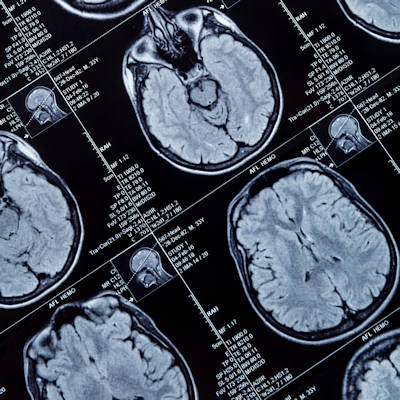

The researchers identified the prevalence and rate of accumulation in the dentate nucleus and globus pallidus on unenhanced T1-weighted MRI from 28 VHL and TSC patients. They compared the signal intensities of the regions to the signal intensity of the pons. They also evaluated the impact of the number of MRI exams, kidney function, and liver function on gadolinium accumulation.

They found the prevalence of accumulation in the dentate nucleus and globus pallidus increased linearly according to the number of gadolinium-enhanced MRI exams and was higher in the VHL group (100%). A significant linear correlation between the number of MRI scans and increased signal intensity was observed in the VHL group.